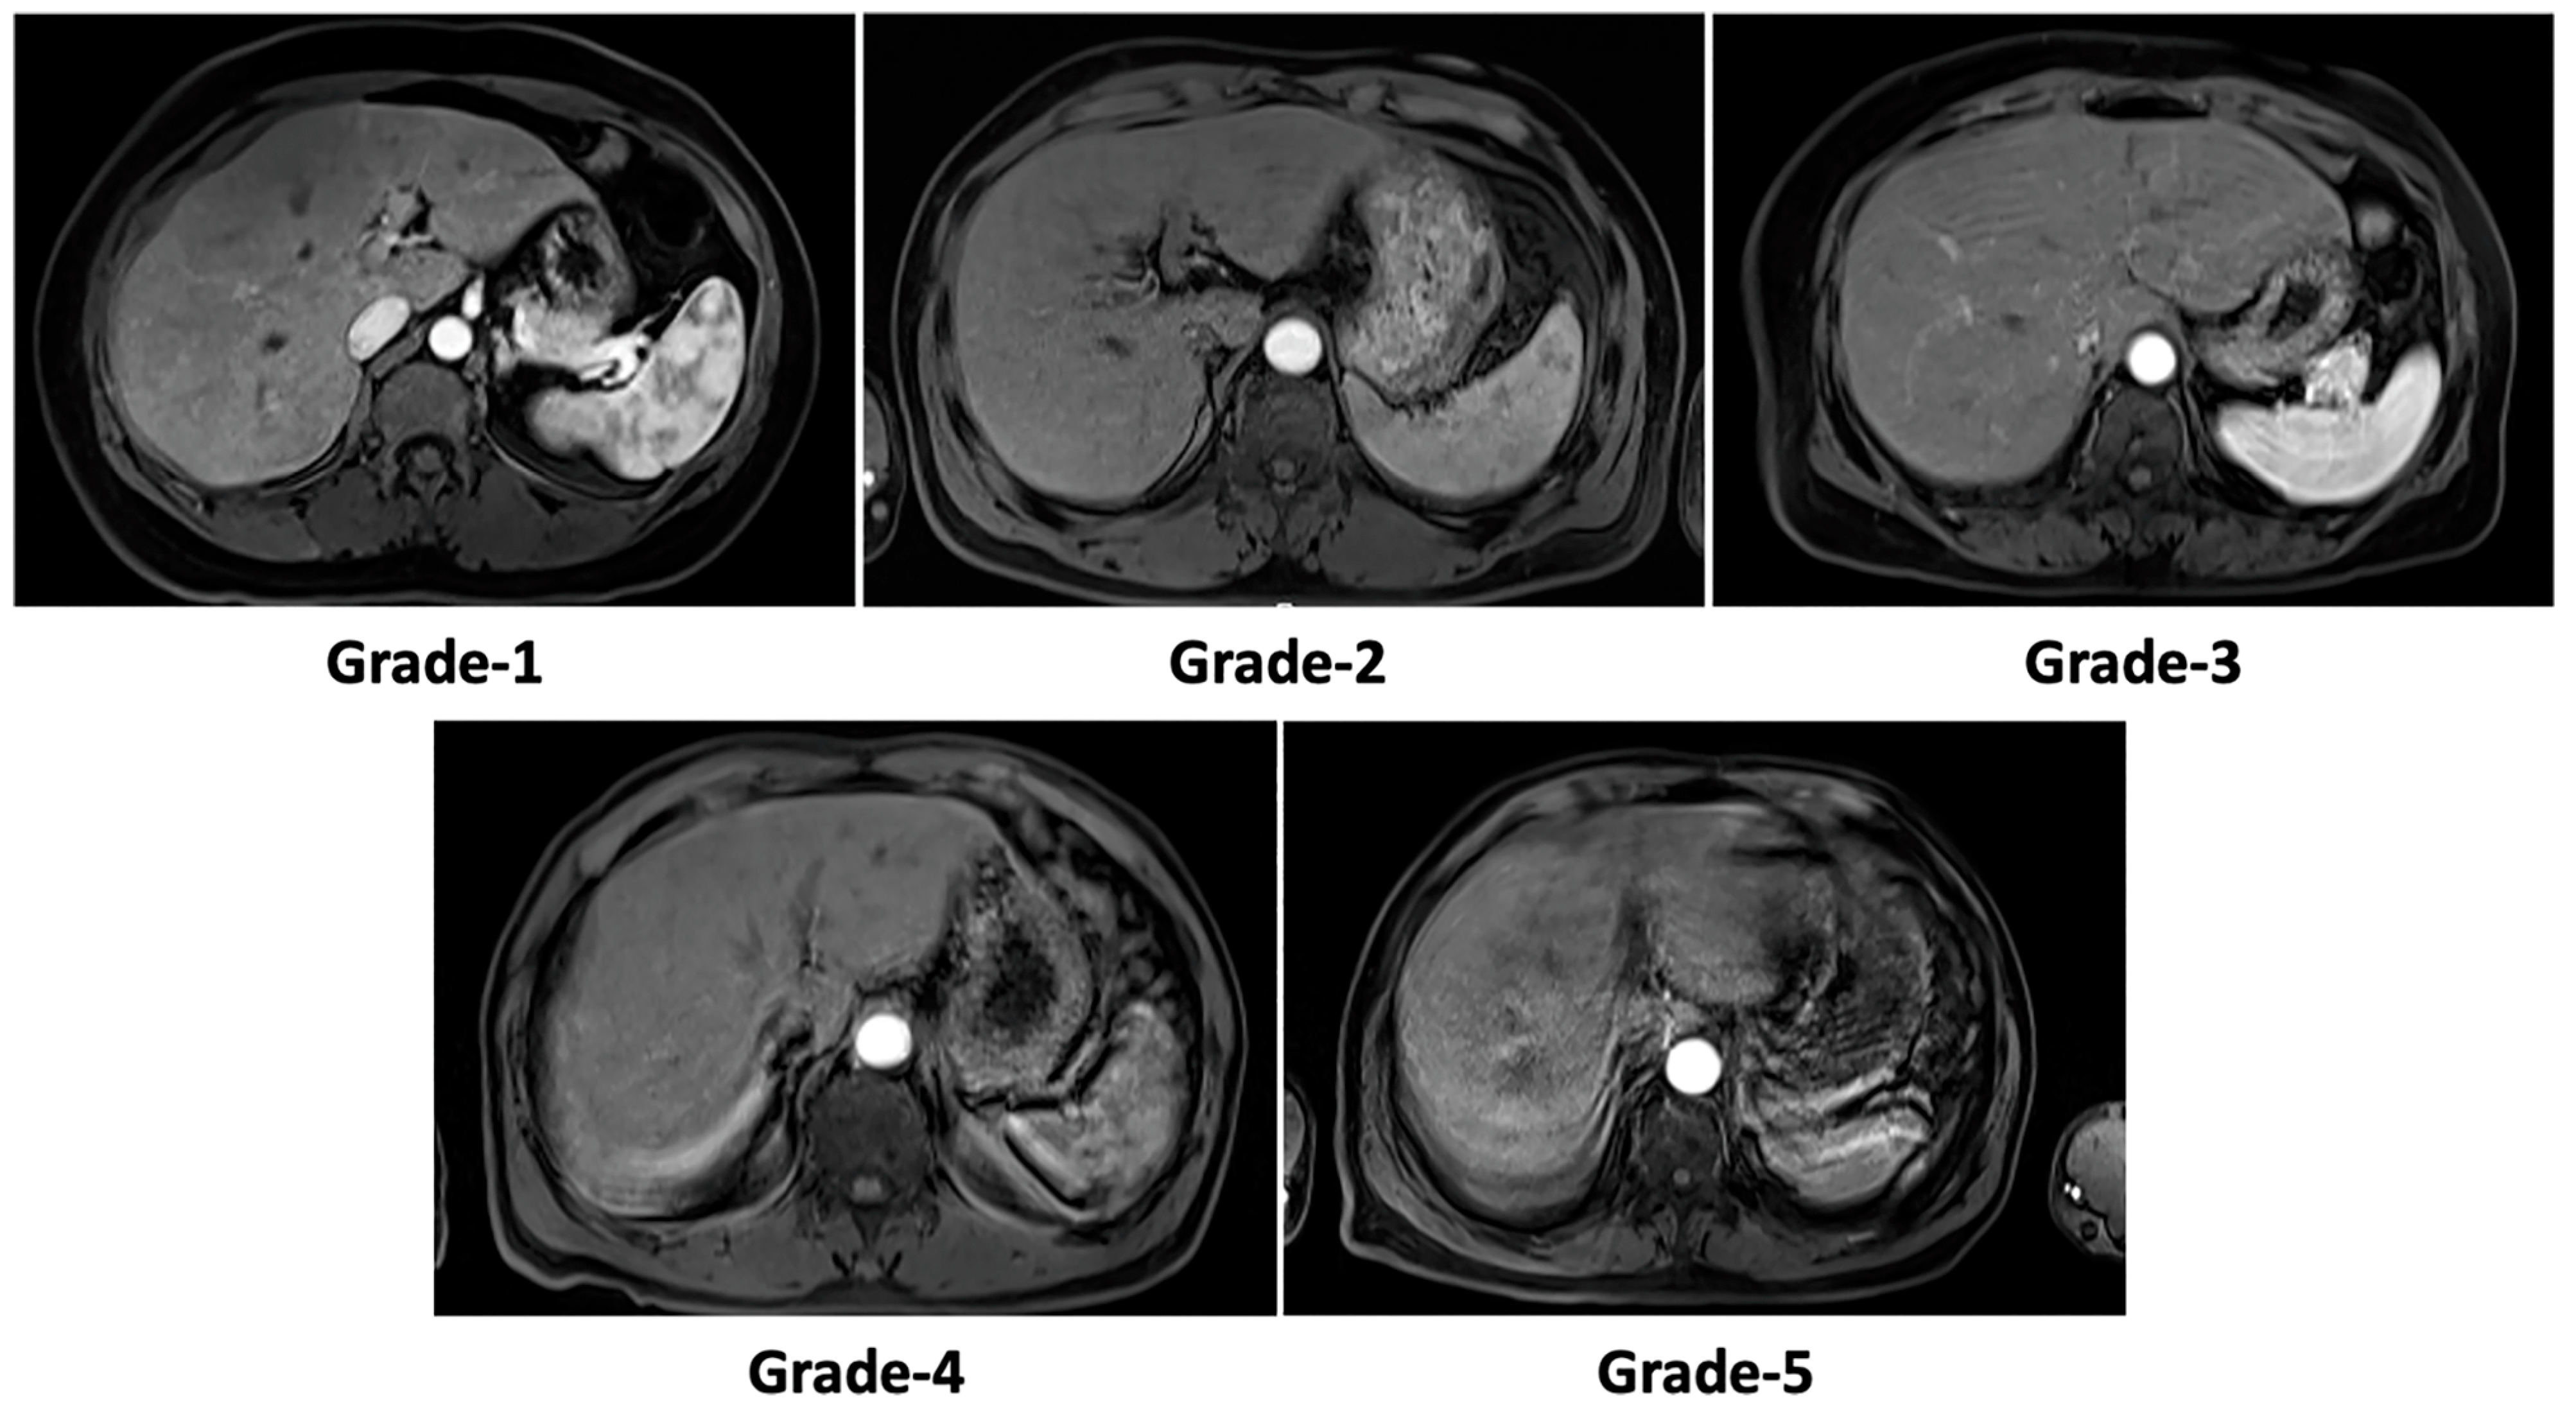

2.3. Motion Artifact Grading

| Motion artifact grades | |

| DR-CycleGAN | 2.7 ± 0.7 * |

| Cycle-MedGAN V2.0 | 3.0 ± 0.9 * |

| Simulated corrupted image data | 4.0 ± 0.8 * |